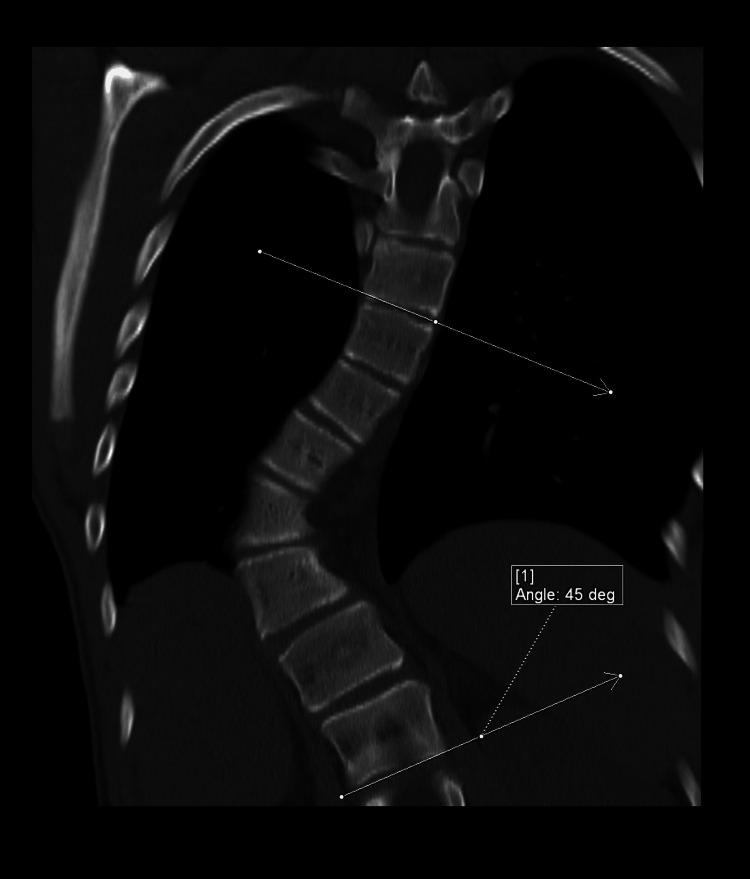

Neurofibromatosis type 1 (NF1) is frequently associated with a multitude of skeletal abnormalities including dystrophic scoliosis. A rare but severe complication of dystrophic scoliosis in NF1 is the herniation of rib heads into the spinal canal, potentially leading to devastating spinal cord compression. We present two pediatric cases of NF1-associated dystrophic scoliosis with intra-spinal herniation of rib heads. Case 1 involves a teenage male with progressive thoracolumbar scoliosis and protrusion of T10 and T11 rib heads into the spinal canal, who underwent successful posterior spinal fusion (T3-L3) with instrumentation, osteotomies, and rib head resection. Case 2 involves a teenage female with progressive thoracolumbar scoliosis and intra-spinal protrusion of T4 and T5 rib heads, who remains neurologically intact despite worsening curvature. Intra-spinal herniation of rib heads is a clinically important complication of NF1-associated dystrophic scoliosis requiring close surveillance. Familiarity with this complication is important as imaging findings may be subtle early on. Surgical management typically involves both spinal fusion and resection of rib heads to prevent neurological compromise, though timing may vary based on symptoms and progression. Multidisciplinary care is essential.

1型神经纤维瘤病(NF1)常伴有多种骨骼异常,包括营养不良性脊柱侧凸。NF1中营养不良性脊柱侧凸的一种罕见但严重的并发症是肋骨小头疝入椎管,可能导致毁灭性的脊髓压迫。我们报告两例NF1相关的营养不良性脊柱侧凸伴肋骨小头椎管内疝的儿科病例。病例1为一名青少年男性,患有进行性胸腰椎脊柱侧凸,T10和T11肋骨小头突入椎管,接受了成功的后路脊柱融合术(T3-L3),包括器械固定、截骨术和肋骨小头切除术。病例2为一名青少年女性,患有进行性胸腰椎脊柱侧凸,T4和T5肋骨小头椎管内突出,尽管脊柱侧凸加重,但神经功能仍保持完好。肋骨小头椎管内疝是NF1相关的营养不良性脊柱侧凸的一种重要临床并发症,需要密切监测。熟悉这种并发症很重要,因为早期影像学表现可能很细微。手术治疗通常包括脊柱融合和肋骨小头切除,以防止神经功能受损,不过手术时机可能因症状和病情进展而异。多学科护理至关重要。